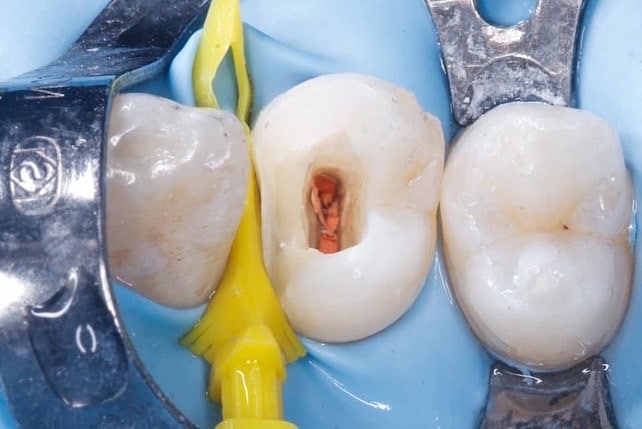

Margin elevation

in this case I’m used a diamond wedge as a matrix to elevate the margin after I finished the margin and replaced the rubber dam after that sandblasting the cavity and repeat the adhesive protocol snd restoring the tooth with bioclear method